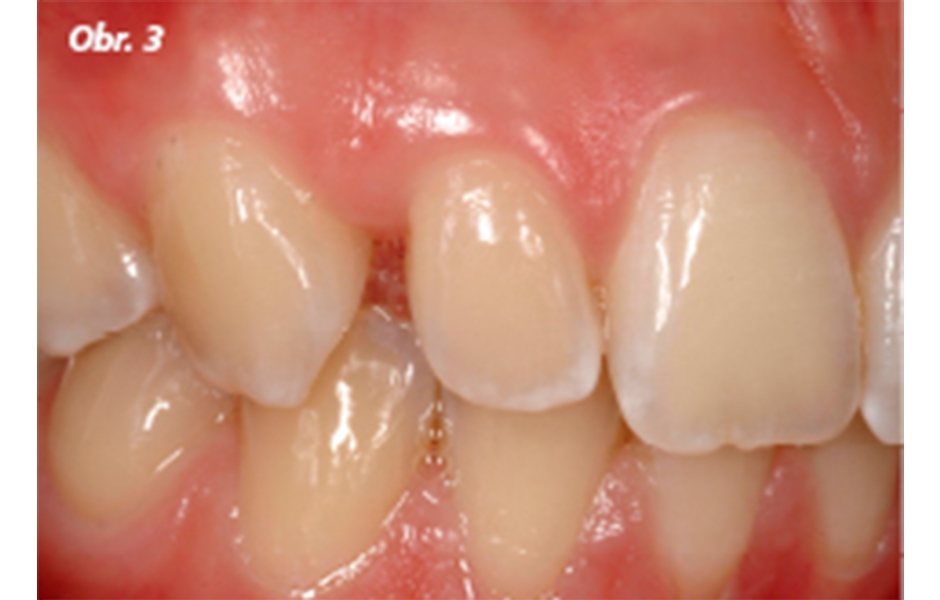

Obr. 3–4: Počáteční stav u mladého pacienta: bilaterální tremata komplikovaná mírnou fluorózou

U pacienta (15 let) bylo ustoupeno od léčení fluorózy, přičemž by bělení bylo pravděpodobně nezbytné, ale s ohledem na riziko citlivosti také kritické (obr. 1–4).

První případ představuje jednoduché použití přímé dostavby při uzávěru tremat u mladého pacienta s tmavým odstínem dentinu a mírnou fluorózou, zvláště viditelnou na incizních hranách řezáků a špičáků (obr. 1).